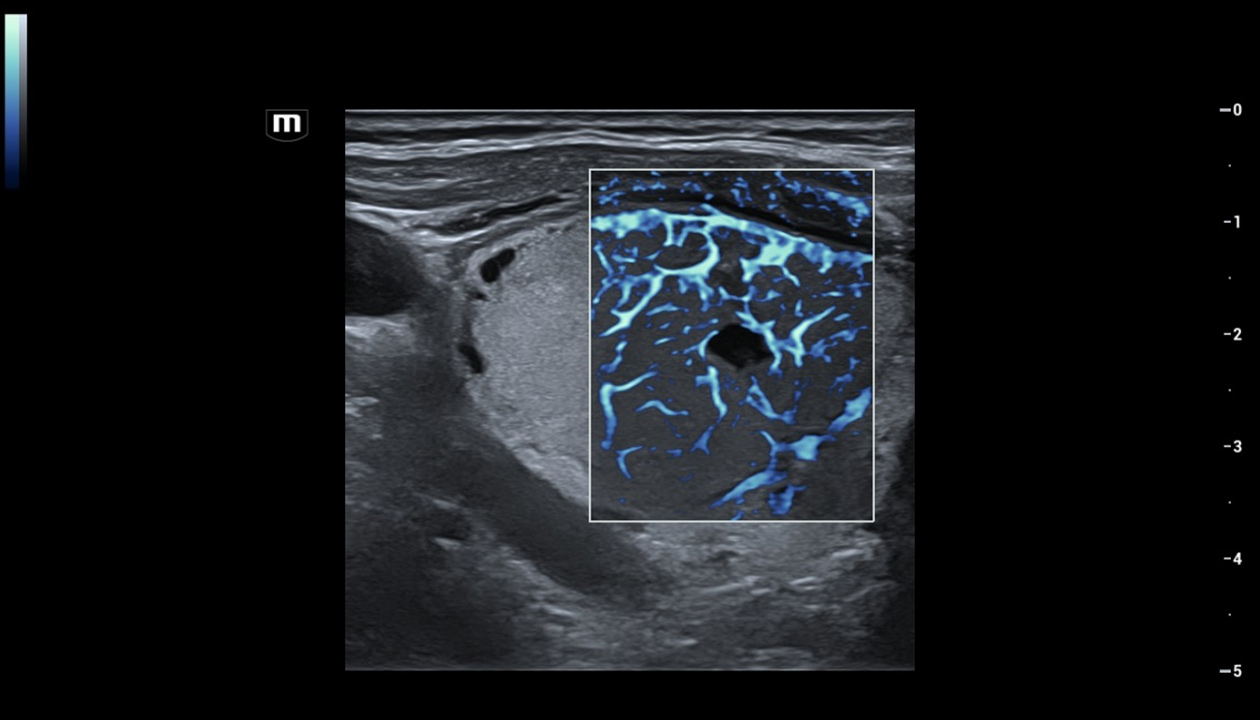

Com tecnologia ZST+

A plataformaZST+ representa um salto extraordinĂĄrio na tecnologia de ultrassom, passando da tradicional forma??o de feixe para o processamento de dados de canal. Essa inova??o revolucionĂĄria supera as compensa??es tradicionais entre resolu??o espacial, resolu??o temporal e uniformidade do tecido, resultando em uma qualidade de imagem inigualĂĄvel com infinitas solu??es de gera??o de imagens.

O Resona I9 fornece solu??es clĂnicas abrangentes para aplica??es dedicadas. Com base em percep??es aprofundadas em diferentes cenĂĄrios clĂnicos, ele oferece inova??es que fornecem aos usuĂĄrios extrema clareza, inteligĂȘncia excepcional e confian?a excepcional no diagnĂłstico.